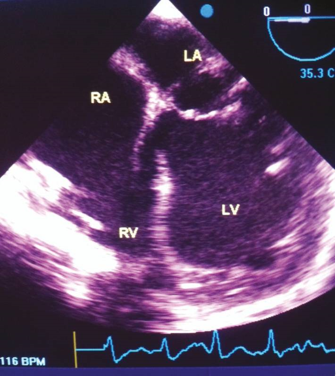

Echocardiography in M-Mode

The initial form of cardiac ultrasound that was developed was M-mode echocardiography ([Figure 1]). In M-mode, a single ultrasonic beam is directed towards the heart, and the reflected signals are displayed on an oscillograph. [11] While M-mode echocardiography does not provide a detailed visualization of the actual anatomy of the heart, it serves a specific purpose in cases where precise measurements of cardiac time intervals during systole and diastole are required. It is also useful when studying rapidly moving targets such as vegetation. [11], [18]